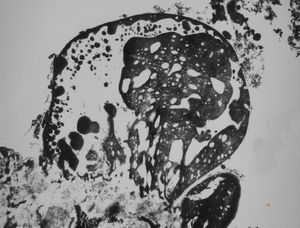

M,10y. | herpetic encephalitis